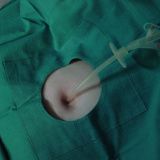

Enfermedades relacionadas con el recto-ano

Hemorroides internas

Fisura anal

Cáncer de recto

Cáncer anal